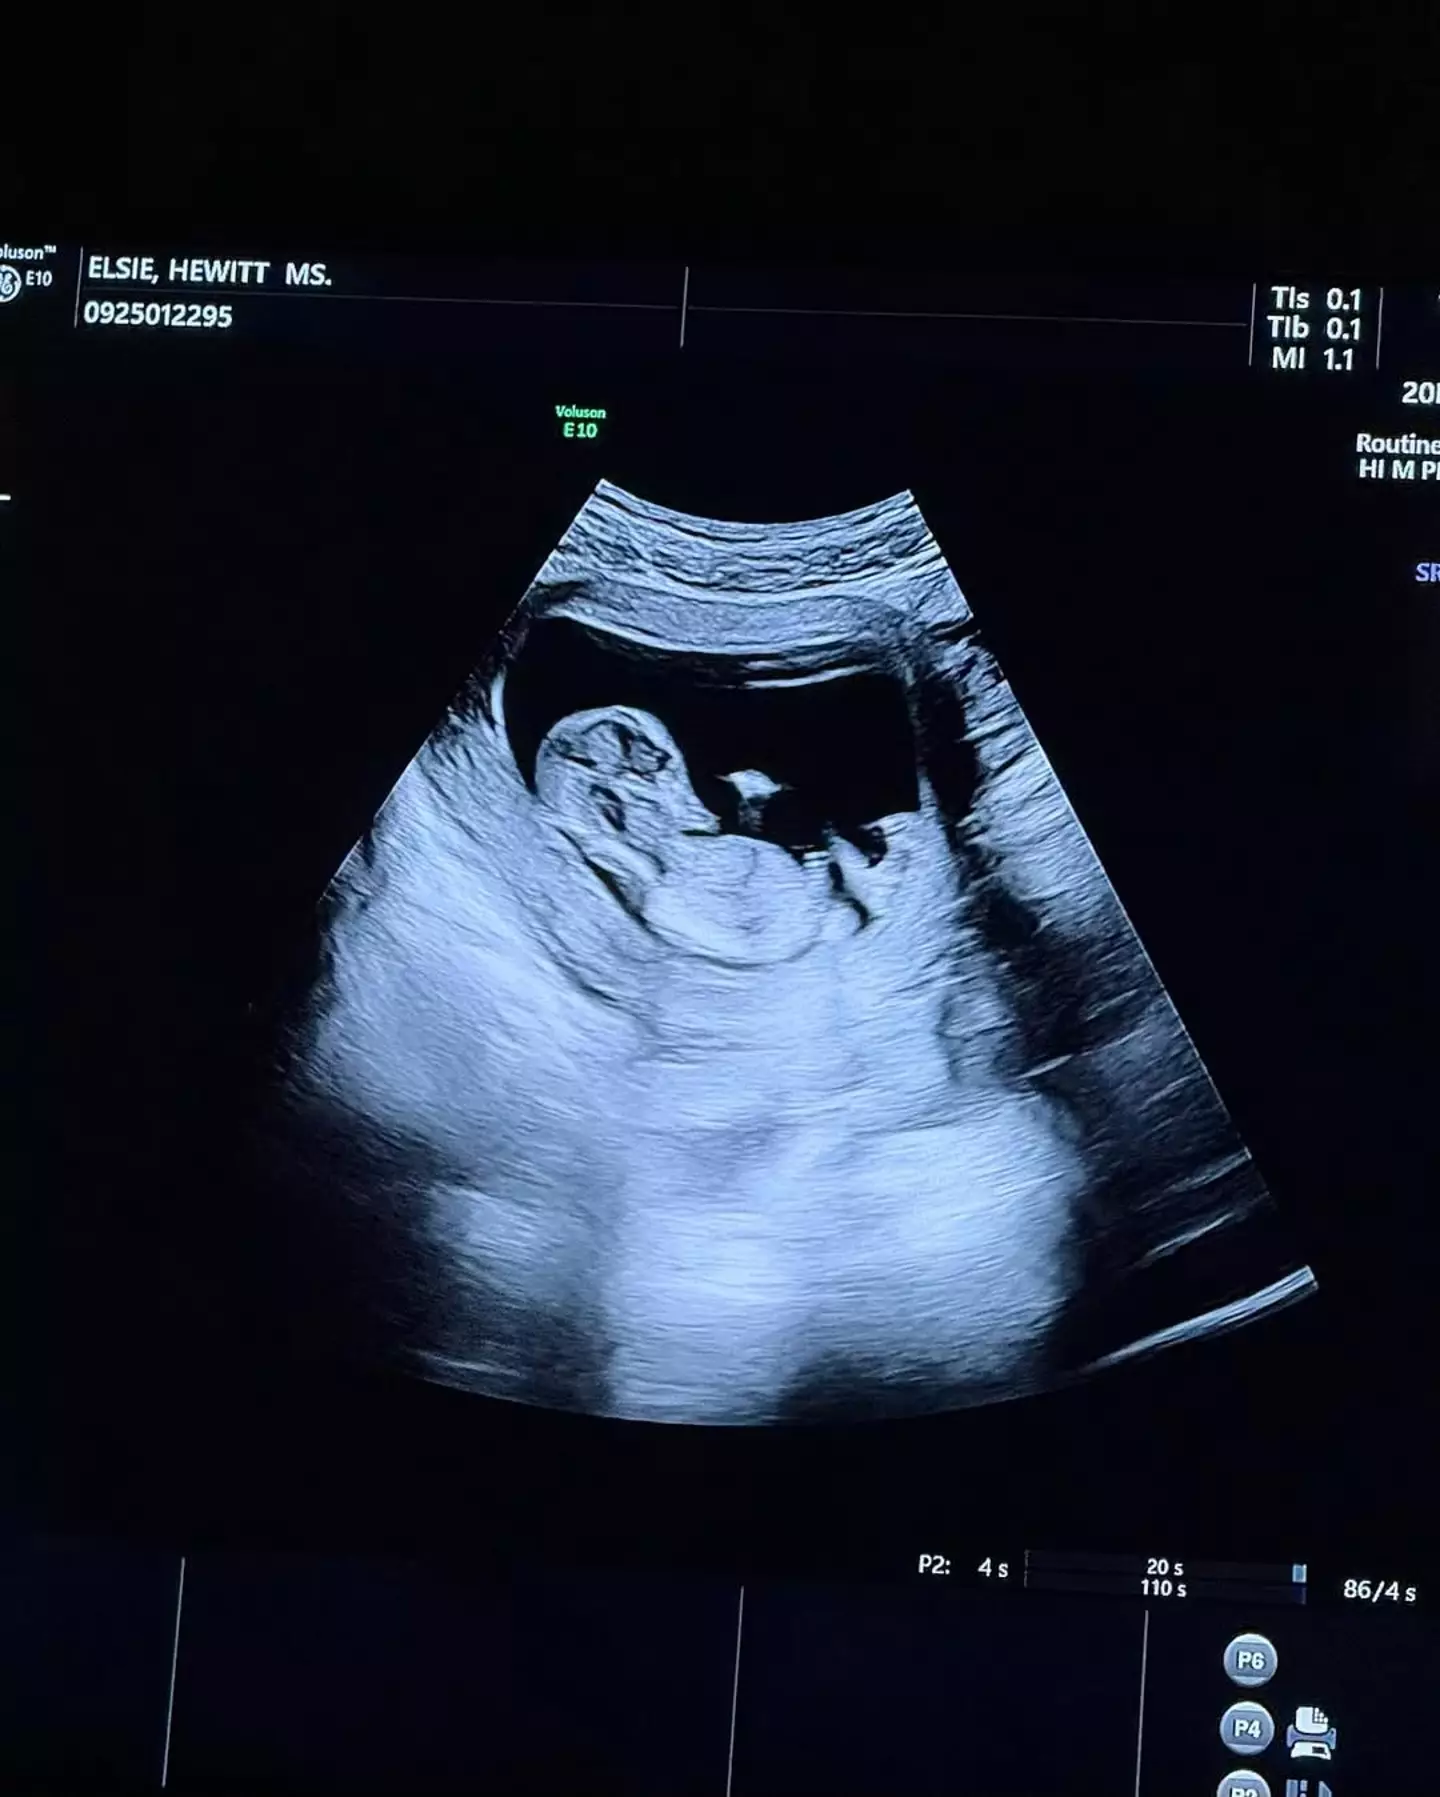

Other posts in the photo dump included a video of Pete holding Elsie's hand going for a sonogram, a picture of the ultrasound scan, the pair holding hands as Elsie stood on a rock, a mirror selfie, the pair wearing skincare face masks and a load of other snaps of the soon-to-be-parents cosying up.